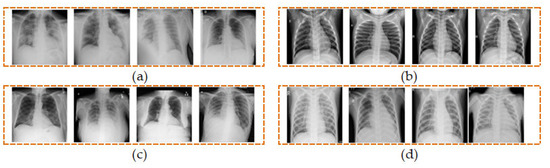

We have utilized a total of 5360 CXR images from the four different classes comprising of COVID-19, normal, lung opacity, and viral pneumonia, each of which contains an equal number of 1340 images as shown in Table 1. Four sample CXR images from each class are shown in Figure 2.

Figure 2.

Samples of CXR images from four classes of (a) COVID-19, (b) normal, (c) lung opacity, and (d) viral pneumonia.